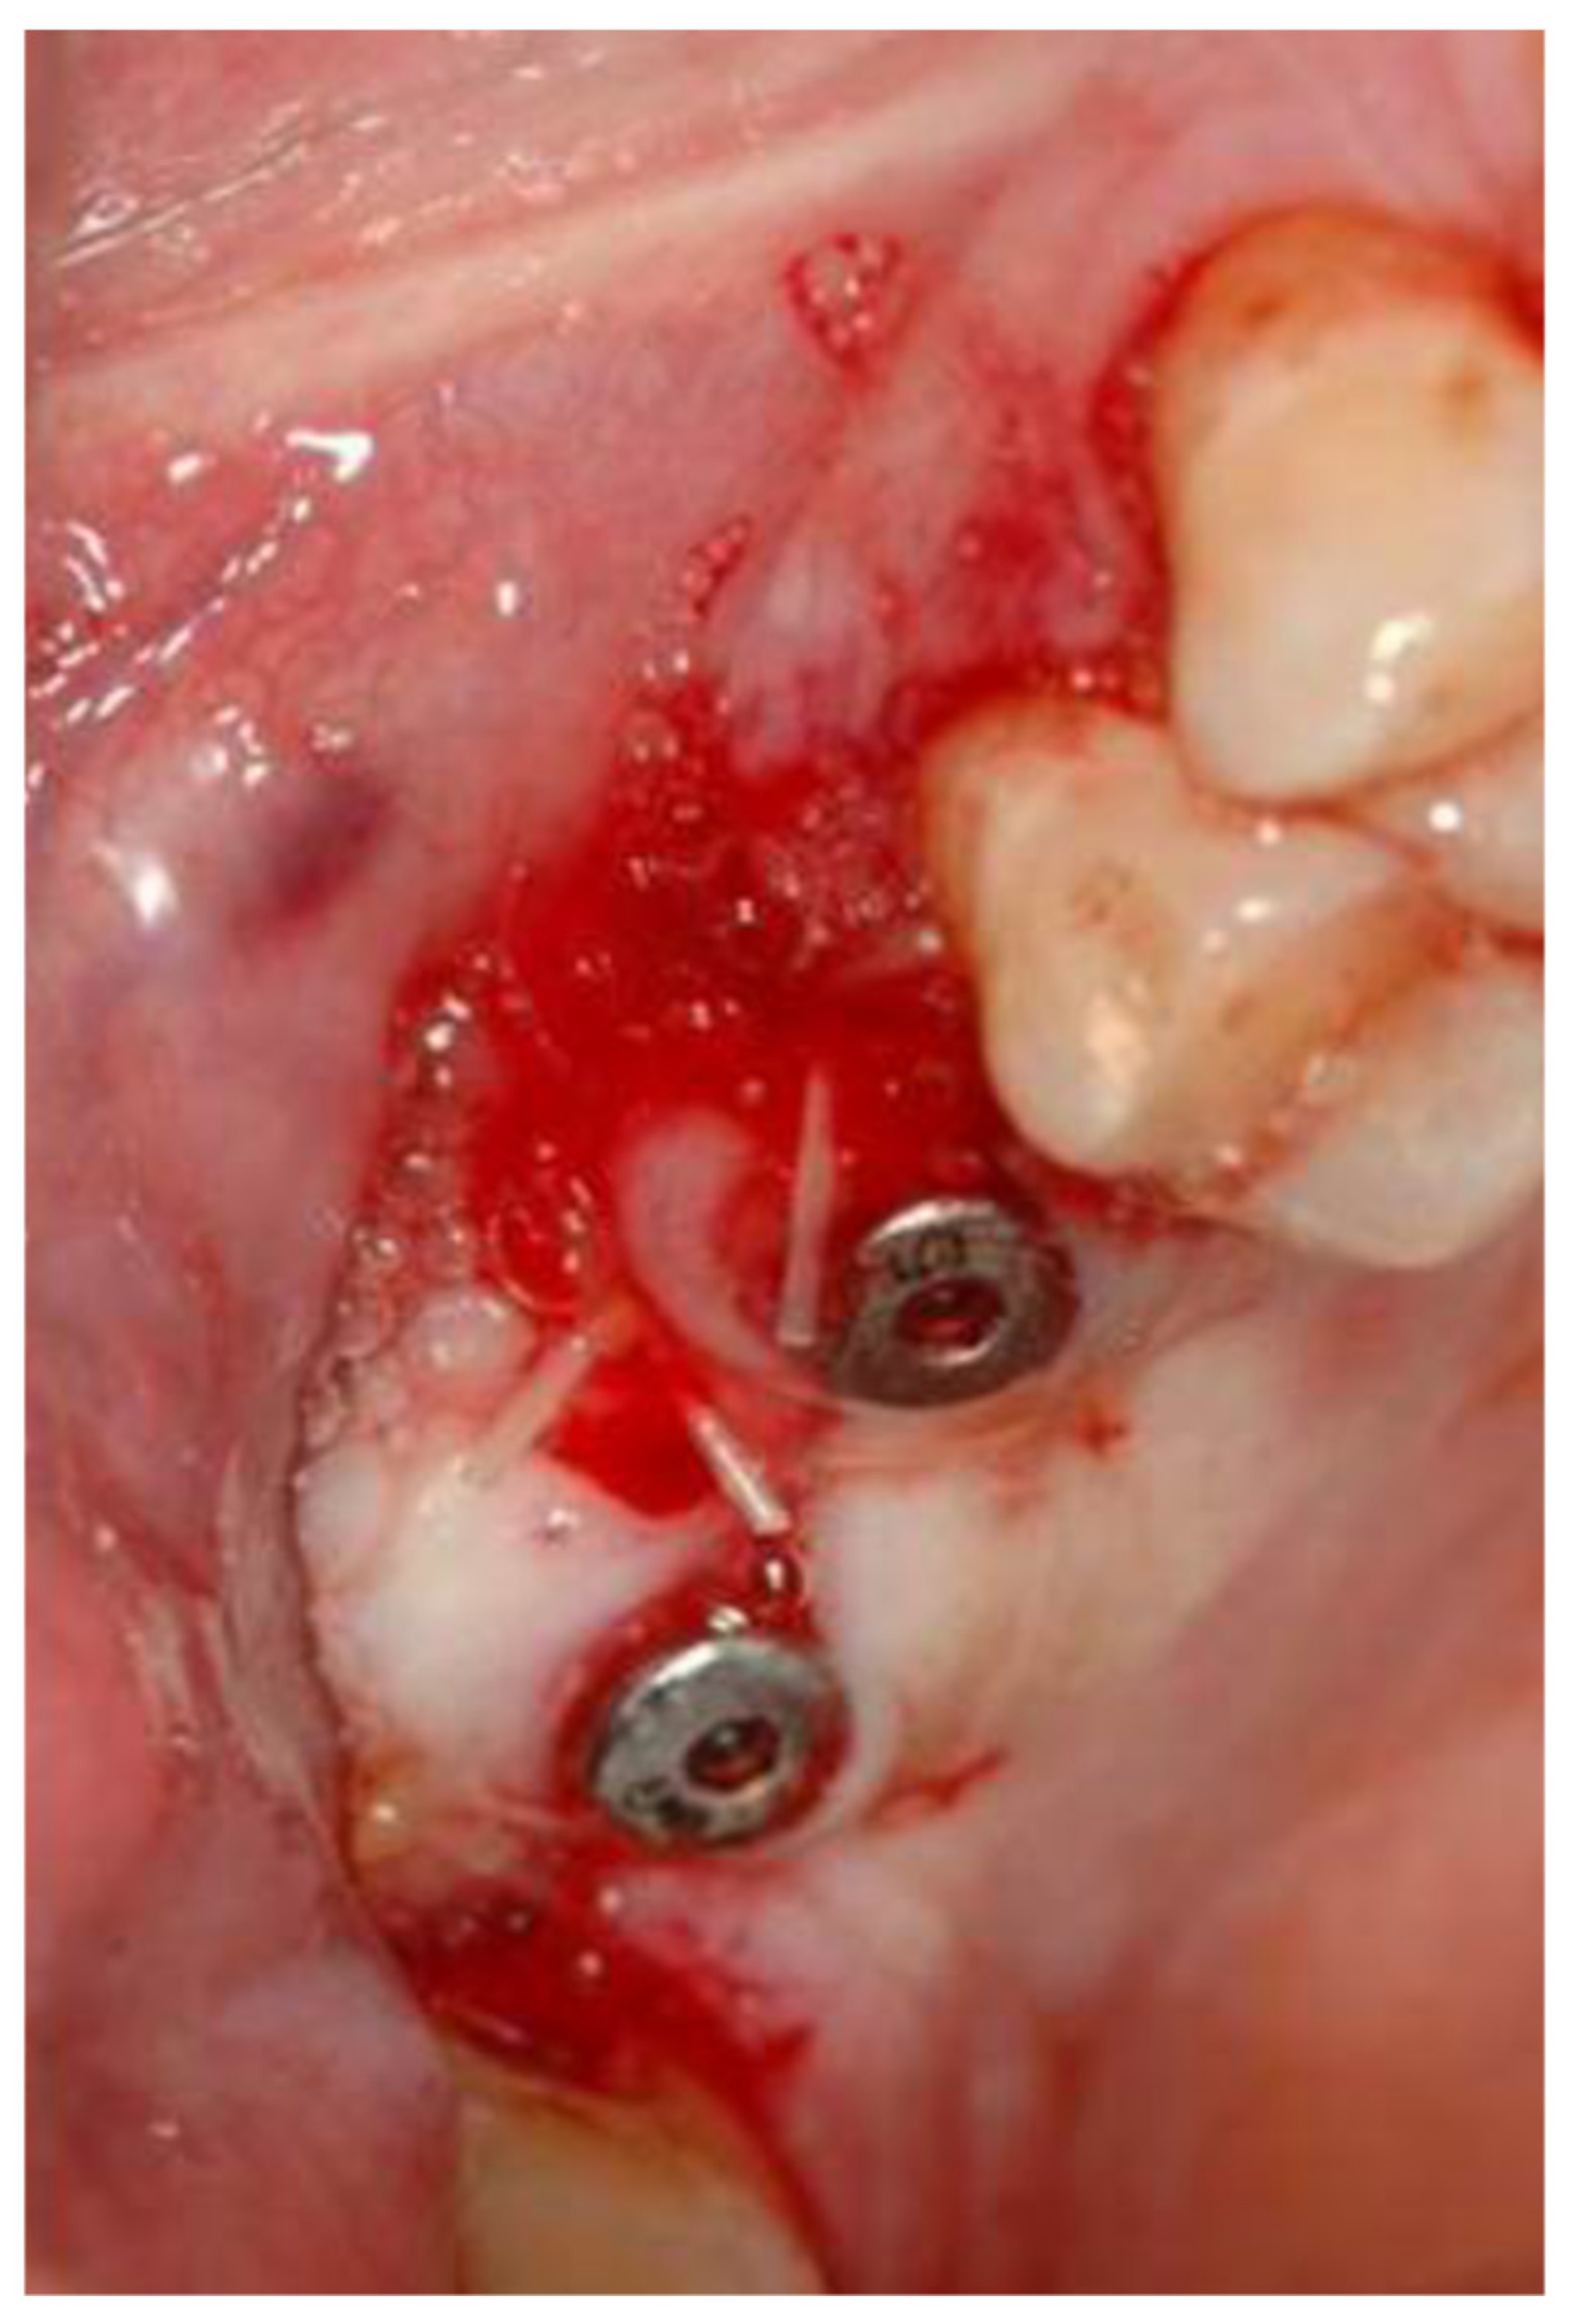

2. Materials and Methods

2.1. Standard Surgical Procedure